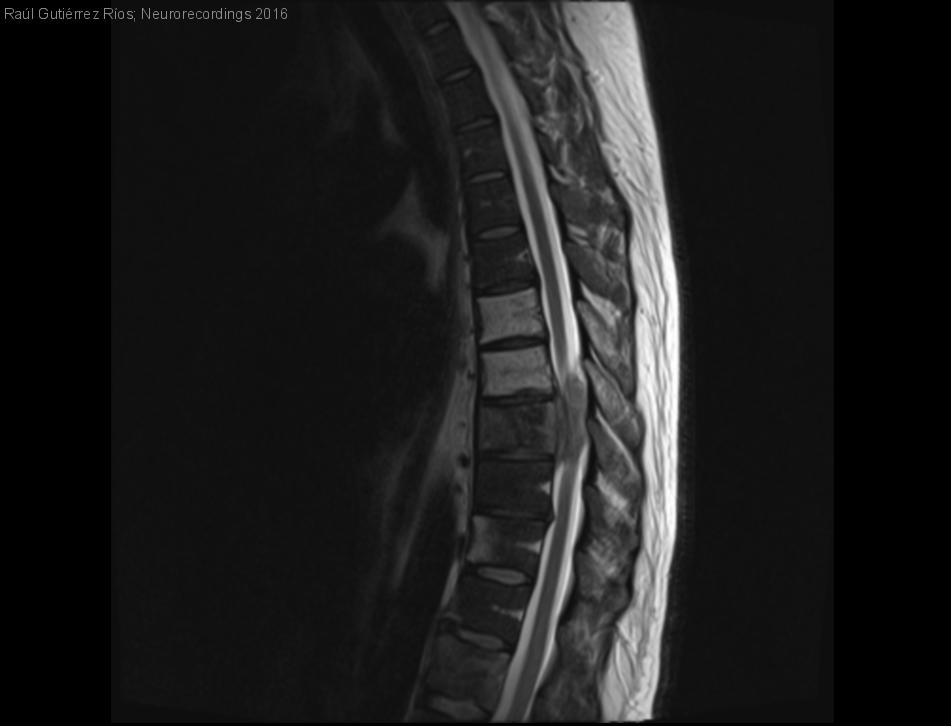

SÍNDROME MEDULAR SUBAGUDO COMO DEBUT DE LINFOMA DE HODGKIN

Hombre | 36 años

Diagnóstico final: LINFOMA DE HODGKIN (variante predominio linfocítico)

Varón de 36 años, sin antecedentes médicos ni quirúrgicos de interés, que ingresa en planta de Neurología procedente del Servicio de Urgencias por paraparesia progresiva. El cuadro se inició 3 meses antes del ingreso con dolor dorsal bajo...